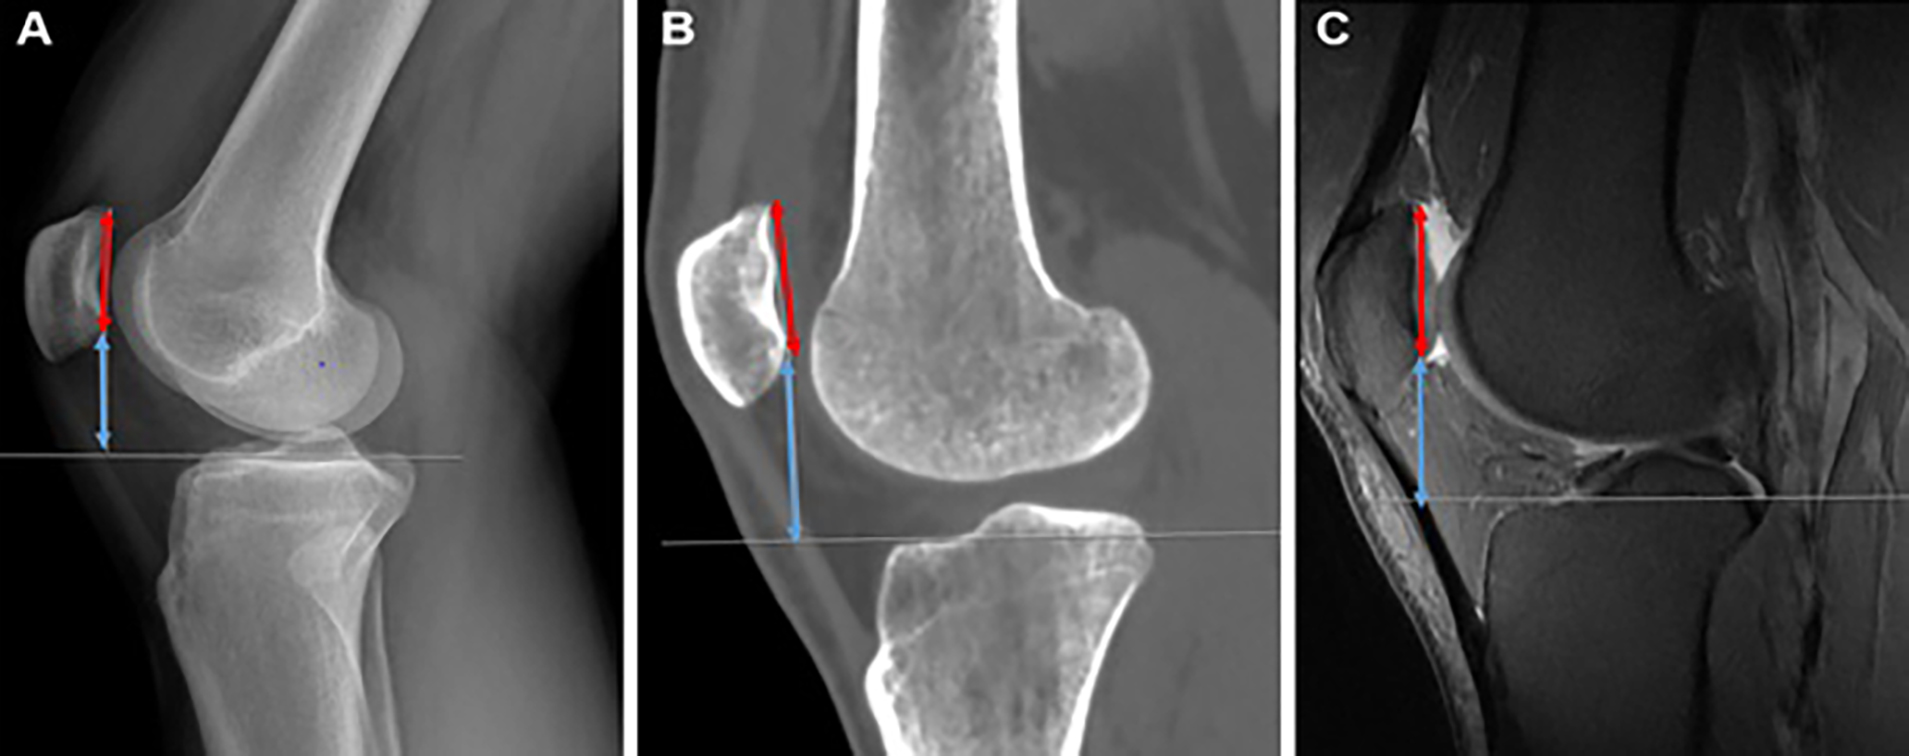

For the Blackburne–Peel (BP) method (Figure 1), the length of the patellar articular surface and the perpendicular distance from its inferior margin to the medial tibial plateau were measured. A horizontal reference line was drawn through the medial tibial plateau to ensure accuracy. The BP ratio was calculated by dividing the perpendicular distance by the length of the articular surface. Standardized methodology ensured consistency across all modalities.

Figure 1

Figure 1. BP = Blackburne–Peel; CT = Computed tomography; MRI = Magnetic resonance imaging; X-Ray=Radiograph. A. Lateral knee X-Ray illustrating the BP method, where the length of the patellar articular surface (red line with arrows on both ends) is measured. In this patient, the tibial plateau appears at a slight inclination relative to the viewer, so a horizontal line is drawn through the tibial plateau to facilitate the visualization of the perpendicular distance (thin white line) from the inferior edge of the patellar articular surface to the tibial plateau surface (blue line with arrows on both ends), B. CT on the bone window showing the BP measurements. The perpendicular distance (thin white line) from the inferior tip of the patellar articular margin to the medial tibial plateau is demonstrated (blue line with arrows on both ends). The patellar articular surface (red line with arrows on both ends) is displayed in this mid-sagittal view, C. Sagittal fat-saturated protondensity MRI demonstrating the measurements of the patellar articular surface (red line with arrows on both ends) and the perpendicular distance (blue line with arrows on both ends) from its inferior edge to the medial tibial plateau surface